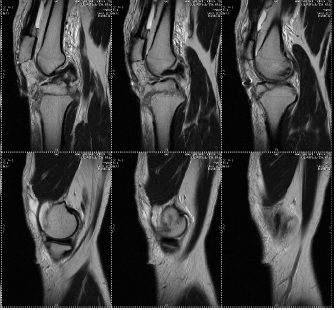

A 26 y-old male sustained a Type IIc Fraser and Type IVb Agarwal and Singh Floating knee injury on the right side. This included displaced intra-articular fractures of the lateral femoral condyle and lateral tibial plateau, a displaced patellar fracture with Grade II ACL tear and PCL sprain, complex tear of the lateral meniscus, and extensor mechanism rupture. Treatment involved external fixation for ipsilateral shaft fractures of the femur and tibia, along with a physiotherapy rehabilitation protocol for associated soft tissue injuries and tension band wiring for the patellar fracture. The patient achieved a good functional outcome after 2 y of follow-up, as depicted in [fig. 1a-d].

Figure 1d: Clinical picture at 2 year Follow up of the same patient with knee flexion, squatting and complete extension